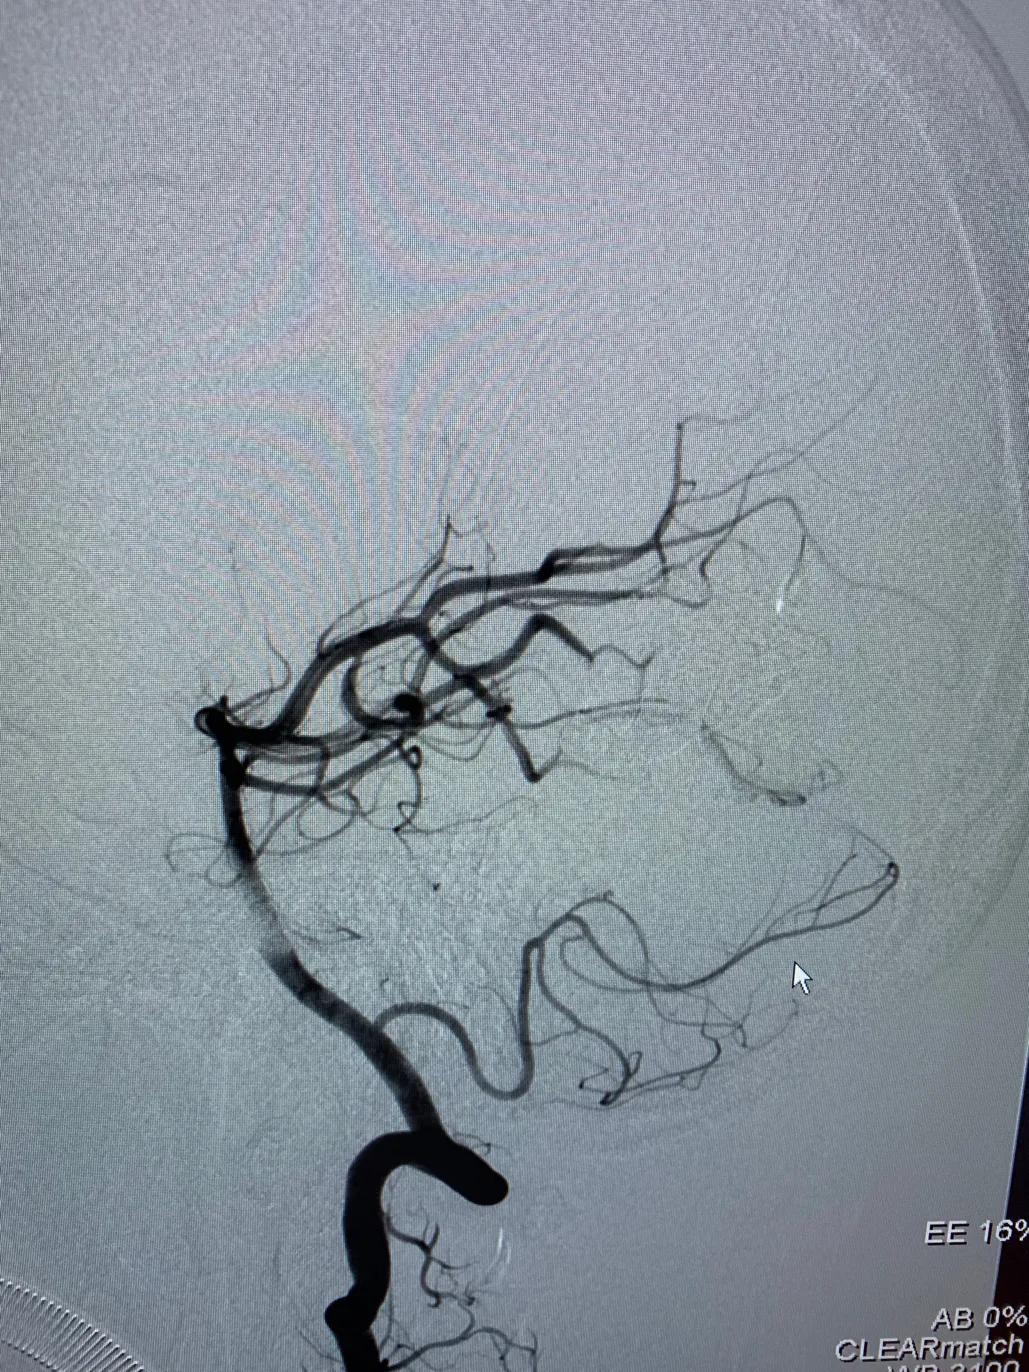

本组部分病例在使用Apollo微导管进行Onyx栓塞时,采用此种技术,可有效的阻止Onyx返流。本病例为一小女孩,右侧枕叶血管畸形,主要供血动脉为右侧大脑后动脉。